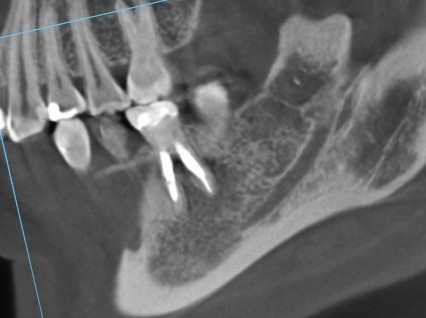

次はこちらの断面へ

遠心の歯根の断面を見てみます。

赤い矢印にありますが、この充填材はすでに根の内側に穿孔しています。

すでに内側に穿孔している充填材は右側の矢印のものです。途中で止まっています。

左側の根管は、左側へ突き抜けて穿孔し、その先が炎症を起こし、黒い影が見られます。

どちらの根の先も膿んで黒い影があります。

つまり、4根管のうち3根管は方向がそれて穿孔しています。